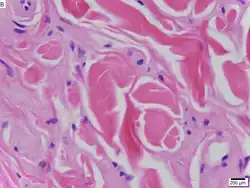

Dado que es la enfermedad de Urbach-Wiethe es una afección autosómica recesiva, los individuos pueden ser portadores de la enfermedad sin mostrar síntomas. La causa de la enfermedad se de a la pérdida de función por la mutación del cromosoma 1 en 1q21, el gen de la proteína de la matriz extracelular 1 (ECM1).[12] Los síntomas dermatológicos se producen por la acumulación de material hialino en la dermis y el engrosamiento de la membrana basal de la piel.[9] La enfermedad de Urbach-Wiethe se diagnostica normalmente por sus manifestaciones dermatológicas clínicas, particularmente las pápulas perladas en los párpados. El descubrimiento de la mutación en el gen ECM1 ha permitido el uso de las pruebas genéticas para confirmar el diagnóstico clínico inicial. La tinción de ácido peryódico de Schiff (PAS) y la tinción inmunohistoquímica también pueden usarse para el diagnóstico[6][13]